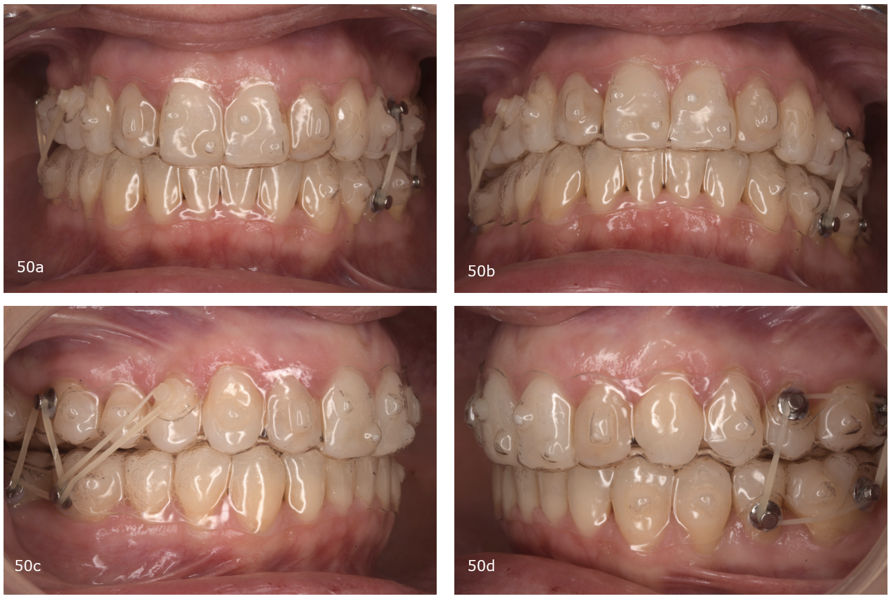

Because the treatment had distributed the spaces between the maxillary incisors, it was decided to provisionally restore the lateral incisors (Fig. 48). After the incisors had been restored with provisional composite, we scanned the patient for new aligners to initiate the second phase. In this phase, we expanded the maxillary and mandibular arches, continued the postero-superior intrusion to close the open bite by mandibular auto-rotation and finalised the alignment (Fig. 49). This stage consisted of 20 pairs of aligners (Fig. 50). We finished the case with a third phase of ten pairs of aligners and incorporated inter-maxillary elastics (Fig. 51).

After treatment, the patient had bilateral Class I molar and canine relationships, correct overjet and overbite, centred midlines and improved arch forms (Fig. 52). Extra-orally, she had improved arch forms, a wider smile, an improved smile line and less gingival exposure (Fig. 53). The lower facial third had been shortened thanks to mandibular antero-rotation, and there was improvement of the upper lip support thanks to the positive torque of the maxillary incisors. In the post-treatment panoramic radiograph, we observed excellent periodontal status, no resorption of the roots and extraction of the maxillary third molars (Fig. 54). In the post-treatment cephalometric tracing, we saw a decrease of the ANB angle, a reduction in the anterior face height, an increase of the facial axis angle, and a decrease in the distance between the soft pogonion and the true vertical line thanks to the anticlockwise rotation of the mandible (Fig. 54). We also found an increase in the inclination of the maxillary incisors and an improvement in the final inter-incisal angle. Concerning her TMJs, the patient remained totally asymptomatic and had a vertical masticatory pattern and a stable arc of closure. The CBCT scan showed well-corticated condyles in the same position as that obtained after the splint therapy (Fig. 56).